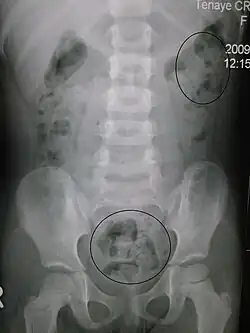

Zaparcie u młodego dziecka widoczne na zdjęciu rentgenowskim | |

Zaparcie (potocznie: zatwardzenie, obstrukcja) – utrudniona lub nieczęsta (rzadziej niż 2 razy na tydzień) defekacja. W skrajnych przypadkach może być śmiertelne. Zaparcie ciężkie to mniej niż 2 wypróżnienia na miesiąc[1]. Zaparcie może być definiowane jako zmiana rytmu wypróżnień lub oddawanie stolca z większym trudem[2].